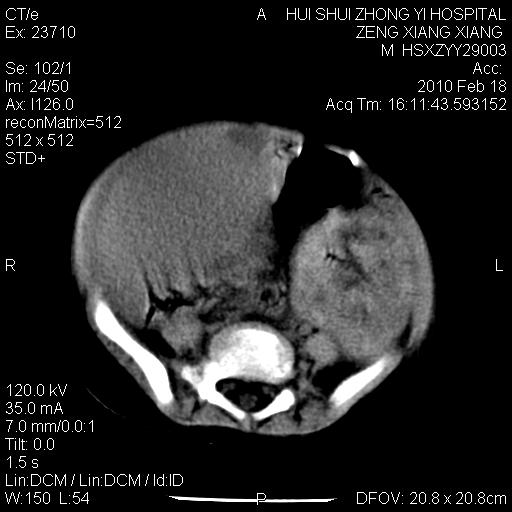

标题: PED3106:男,2岁,腹胀1月。 [打印本页]

标题: PED3106:男,2岁,腹胀1月。

定位腹膜后,肾上腺来源;

定性:恶性神经源性,肾上腺神经节母细胞瘤可能性大。

鉴别:肝母、肾母、肝脏中胚层错构瘤。

依据:年龄、有钙化,肾脏及肝脏受压移位。

肝母细胞瘤可能性大,右肾形态大体可见,不支持肾母细胞瘤,右肾移位不明显,肾上腺神经母细胞瘤可能性不大。